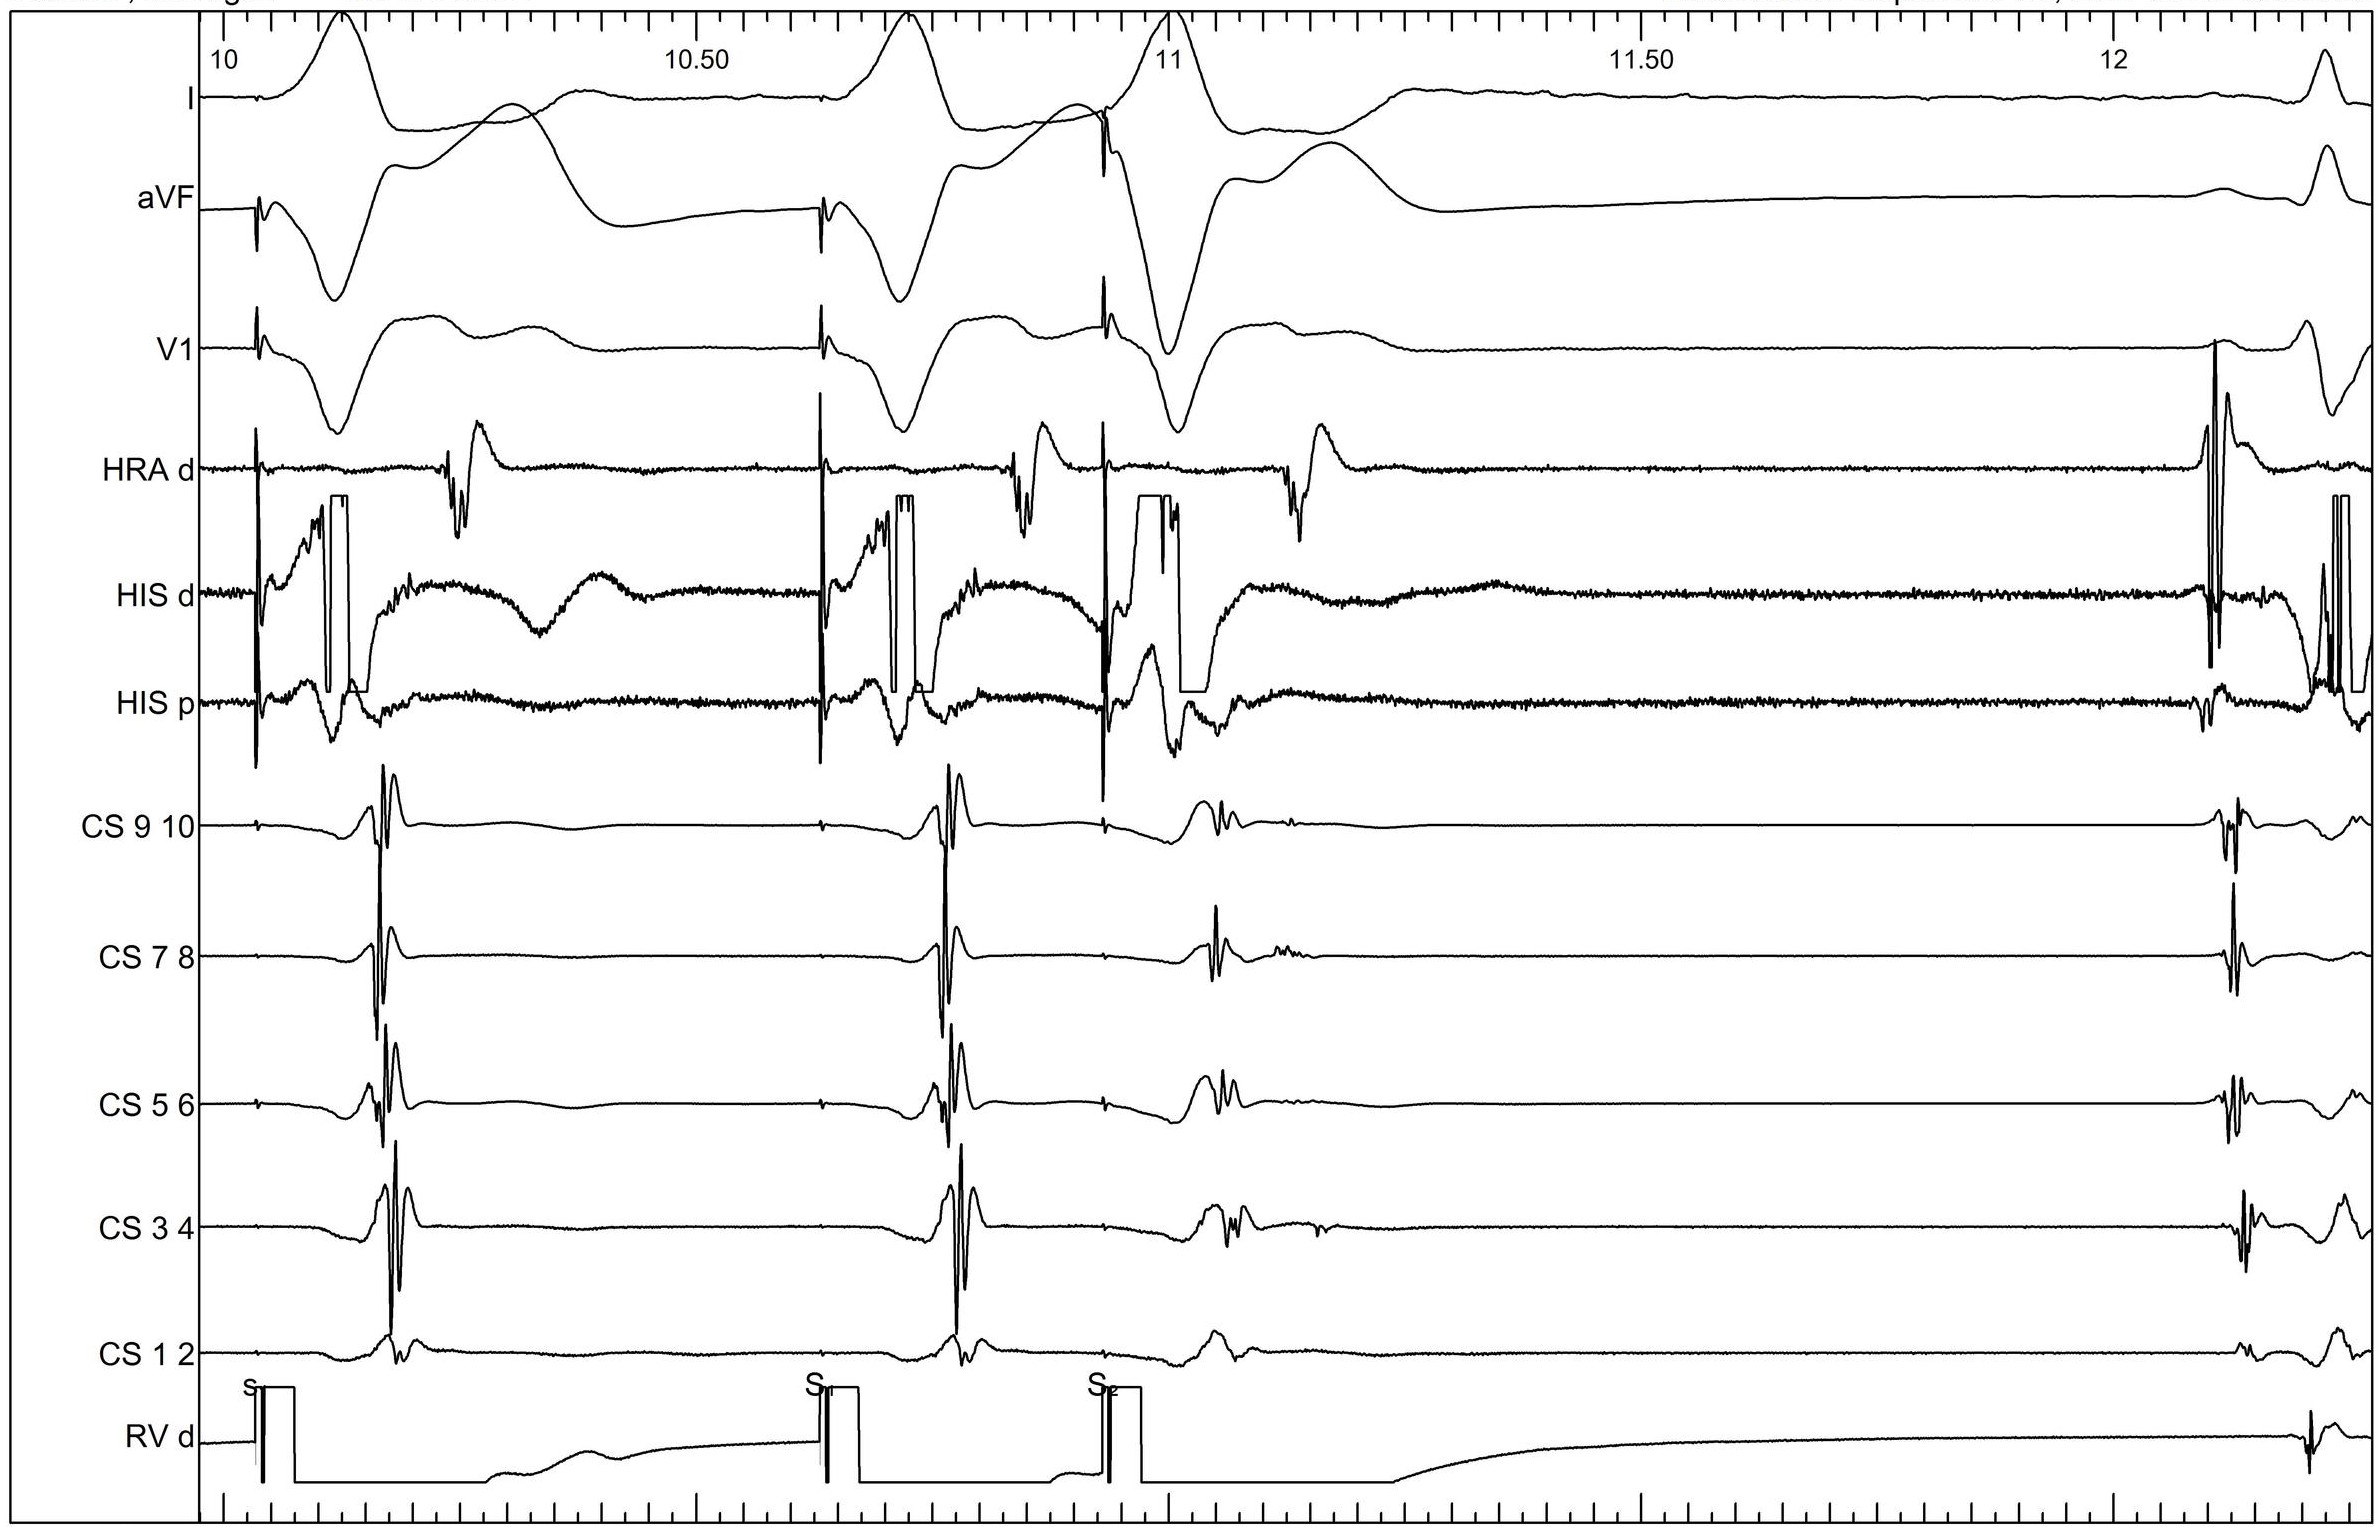

Ventricular burst pacing

05_vop_termination.jpg

Ventricular overdrive - Beginning

06_vop_onset.jpg